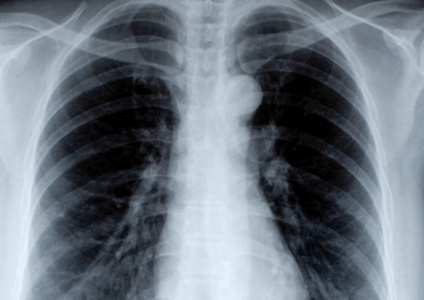

• RÖNTGENDIAGNOSTIK DER LUNGE